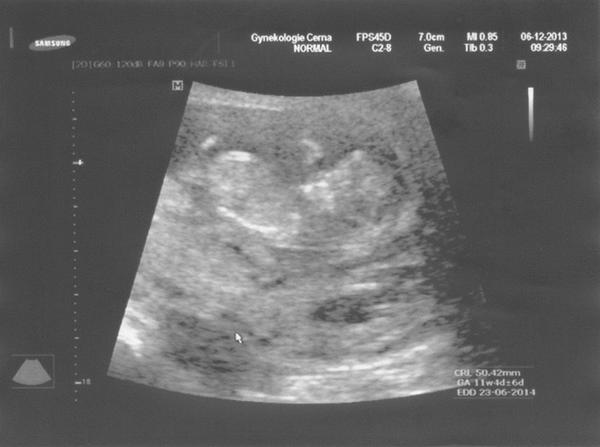

zajtra začíname 8tt pfuj pfuj nech je úspešný ako tie pred name!!! v 9tt ideme k lekárovi jupííííííííí